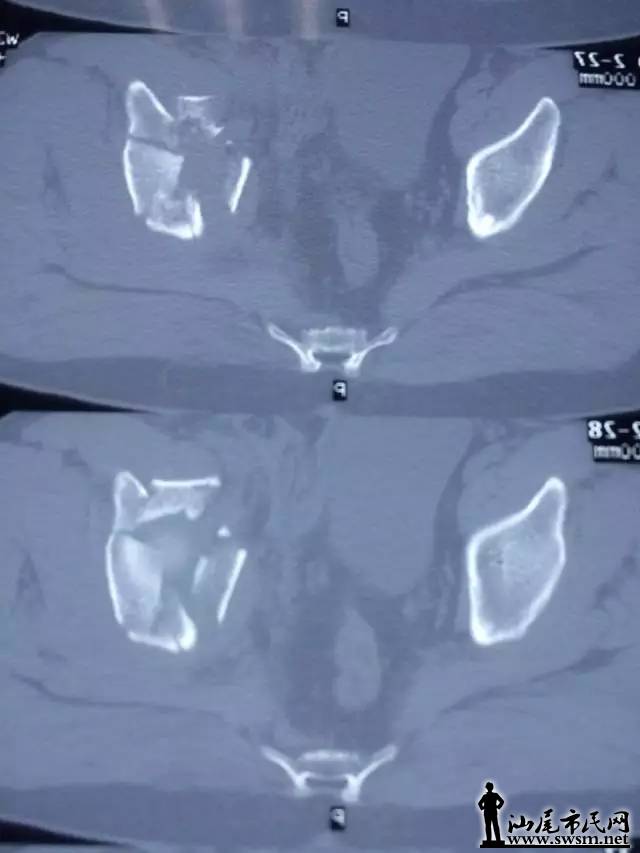

海丰县中医医院骨三科团队,利用3D打印技术,事先将患者的骨盆CT扫描数据输入电脑,再用先进的3D打印机,以1:1比例打印出熊先生的仿真骨盆模型。预先为其设计好最佳的手术治疗方案。                   640.webp.jpg                                                                          ( 上图:术前DR片)                                                                                                                   640.webp (1).jpg       640.webp (2).jpg                                                 (上图:术前CT片)

骨三科团队手术前在仿真骨盆进行虚拟手术,设计好钢板旋转的最佳位置、螺钉植入的最佳方向,并进行钢板、螺钉长度的数据测量,螺钉方向导航模块的设计及钢板预弯等一系列术前体外模拟手术,所有准备工作操练完毕,最后才正式为其施髋臼骨折复位钢板内固定手术。                                     640.webp (3).jpg                                                                                  (上图:虚拟手术,预弯钢板、测螺钉长度等数据)

由于钢板放置最佳位置、螺钉长度等已按照伤者的身体进行过精准的测量,减少了不必要的显露,手术切口仅8厘米;手术中也不需要反复预弯钢板和测定螺钉,使得手术时间大大减少。真正的内固定手术不到1小时,另外前后出血不足600毫升,大大节约血源、减少输血风险等,提高了手术的安全性,减少了伤者的痛苦。                                                                                        640.webp (4).jpg 640.webp (5).jpg 640.webp (6).jpg 640.webp (7).jpg                                                                          从术后复查钢板位置及螺钉植入方向、长度与术前3D打印模拟手术完全匹配,患者术后第二天便可以自行翻身、半坐等,良好的疗效受到了患者及其家属的称赞。